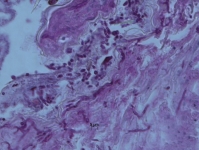

| Substrate: | fatal disseminated pustular infection of the skin, tentacled snake (Erpeton tentaculatum); histopathology + for hyphae and arthroconidia | Location: | CANADA Ontario, Toronto, Toronto Zoo (GEO: 43.819,-79.18) |

| Characters: | HUMAN/ ANIMAL PATHOGEN fatal fungal dermatitis in captive-bred tentacled snakes (Erpeton tentaculatum) - Bertelsen M.F, Crawshaw JG, Sigler L, Smith DA, J Zoo Wildlife Med 36:82-87, 2005 // HUMAN/ ANIMAL PATHOGEN third of 4 snakes that died, multiple foci of skin infection - // MOLECULAR SYSTEMATICS phylogeny of Nannizziopsis and reptile pathogens belonging to the CANV complex - Sigler L, Hambleton S, Pare JA, J Clin Microbiol 51:3338-3357, 2013 (Click for publications citing UAMH 10199) |